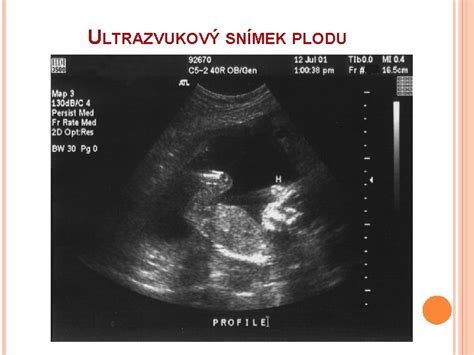

Ultrazvukové vyšetrenie

Presný týždeň gravidity sa upresňuje ultrazvukovým vyšetrením. Na základe stupňa vývoja dieťatka prístroj presne určí ukončený a prebiehajúci týždeň gravidity (napr. 7+3 znamená: ukončený siedmy týždeň gravidity a prebiehajúci ôsmy, z ktorého zatiaľ uplynuli len tri dni).

Termín pôrodu najpresnejšie určí gynekológ pomocou ultrazvukového vyšetrenia, pričom najspoľahlivejšie výsledky sa získajú v 11. až 13. týždni tehotenstva. Vek bábätka sa určí na základe merania CRL (CRL = crown-rump length), čo je vzdialenosť od temena hlavy po kostrč bábätka, udávaná v milimetroch.